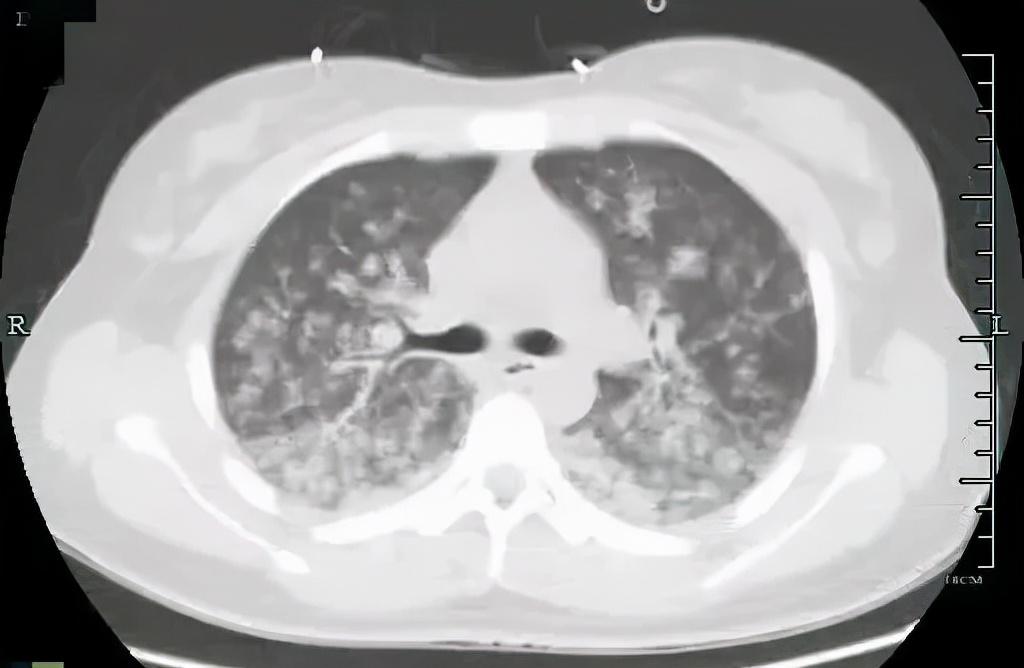

两种原因造成的结果相似,但调节方案截然不同。根据小月的肺动脉CTA、肺部CT等检查结果显示,小月为肺脂肪栓塞,此时小月的肺部已是白茫茫一片,就像暴风雪一样,脂肪进入她肺部,刺激血管发生痉挛,产生严重的炎症因子风暴!